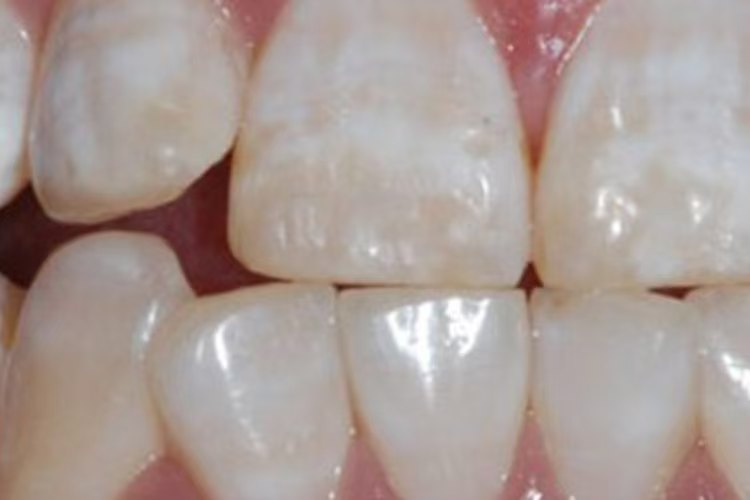

1.轻度(白垩型): 牙面上出现不透明的黄白相间的斑块或条纹,表面粗糙。

· 树脂渗透术: 一种微创技术,用透明树脂渗入多孔釉质,有效遮挡白垩色斑,效果自然。